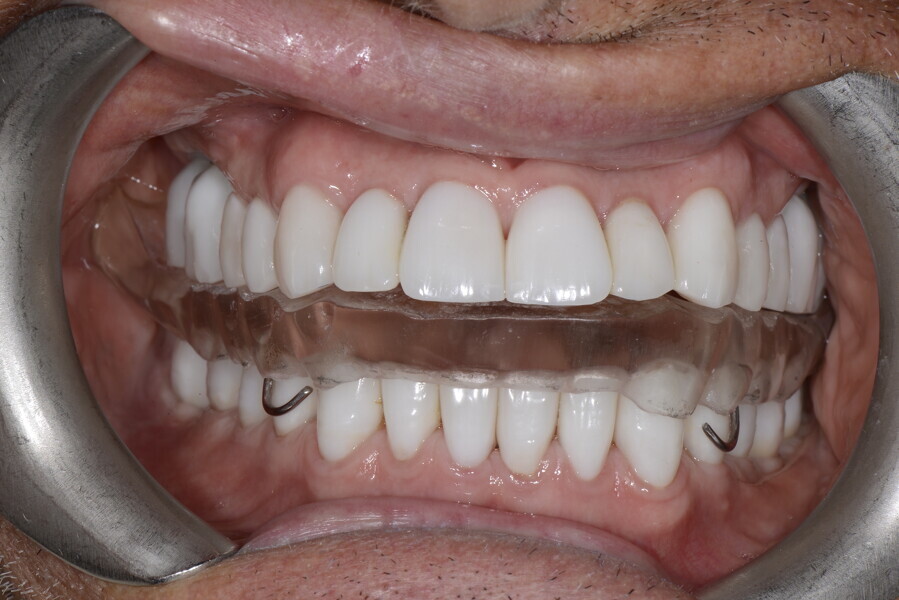

During the first visit, we checked the centric relation with cotton rolls, eliminating the posterior mesialising precontact and then performed a direct composite aesthetic and functional mock-up in this new position, not only to motivate the patient regarding the final result but also to help him understand better overall why tongue therapy, tooth alignment and dental resurfacing for augmentation of the vertical dimension of occlusion were required (Figs. 14 & 15).

This patient, like all patients requiring interdisciplinary rehabilitation, had to first undergo periodontal treatment and caries restoration (Fig. 17). At the same time, it was important to rehabilitate swallowing with Froggymouth and relax the masticatory muscles and relieve the TMJs with an occlusal device. We could then study the orthodontic treatment plan using Invisalign ClinCheck (Align Technology) and showed the treatment plan to the interdisciplinary team and to the patient (Fig. 18). We were then able to create the correct sequence of orthodontic treatment, bone augmentation and implant surgery needed for the posterior edentulous spaces.

After the first phase of aligner treatment, we had achieved better inter-arch coherence, better maxillary arch expansion, and some space for improving the anterior tooth proportions restoratively (Fig. 19). We then temporarily restored the anterior teeth directly with composite, closing the spaces, improving the tooth proportions and further increasing the maxillary arch expansion (Fig. 20). We used restorative arch expansion to reduce the orthodontic destabilisation of the teeth to achieve the correct inter-arch coherence and retain the teeth in the cortical bone.38 A refinement aligner phase was undertaken to improve the final alignment of the gingival zenith and to improve the inter-arch coherence (Fig. 21). The periods of the first orthodontic phase and of the refinement were used to augment the mandibular and maxillary bone and to place the implants (Fig. 22). At the end of the orthodontic treatment, the case was finalised with ceramic veneers in the anterior area and temporary restorations on the implants in the posterior area (Figs. 23–26).